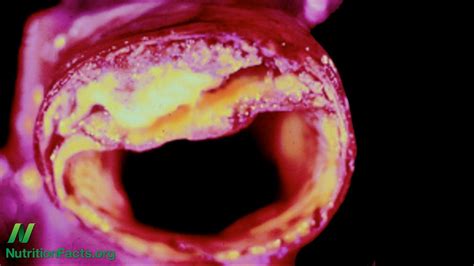

Treatment for an unruptured brain aneurysm may be appropriate in some cases and may prevent a rupture in the future. This type of hemorrhagic stroke is called a subarachnoid hemorrhage. Many have no symptoms and are not dangerous. A sudden, severe headache is the key symptom of a ruptured aneurysm. An aneurysm occurs when an artery's wall weakens and causes an abnormally large bulge. Blurred or double vision 5. Common signs and symptoms of a ruptured aneurysm include: A number of factors can contribute to weakness in an artery wall and increase the risk of a brain aneurysm or aneurysm rupture.

Arteries are blood vessels that carry blood from your heart to your organs. Change in vision or double vision 4. A brain aneurysm can leak or rupture, causing bleeding into the brain (hemorrhagic stroke). A number of factors can contribute to weakness in an artery wall and increase the risk of a brain aneurysm or aneurysm rupture. An unruptured brain aneurysm may produce no symptoms, particularly if it's small.

An excessive localized enlargement of an artery caused by a weakening of the artery wall. This type of hemorrhagic stroke is called a subarachnoid hemorrhage. Sudden, extremely severe headache 2. A brain aneurysm can leak or rupture, causing bleeding into the brain (hemorrhagic stroke). Brain aneurysms are more common in adults than in children and more common in women than in men. Talk with your caregiver to ensure you understand the best options for your specific needs. If the aneurysm ruptures, you might feel sick to your stomach, or suddenly develop an intense pain in your back or abdomen. Complications that can develop after the rupture of an aneurysm include: It also increases pressure inside the skull. Most brain aneurysms, however, don't rupture, create health problems or cause symptoms. A number of factors can contribute to weakness in an artery wall and increase the risk of a brain aneurysm or aneurysm rupture. Sudden, extremely severe headache a more severe rupture often follows leaking. See full list on mayoclinic.org